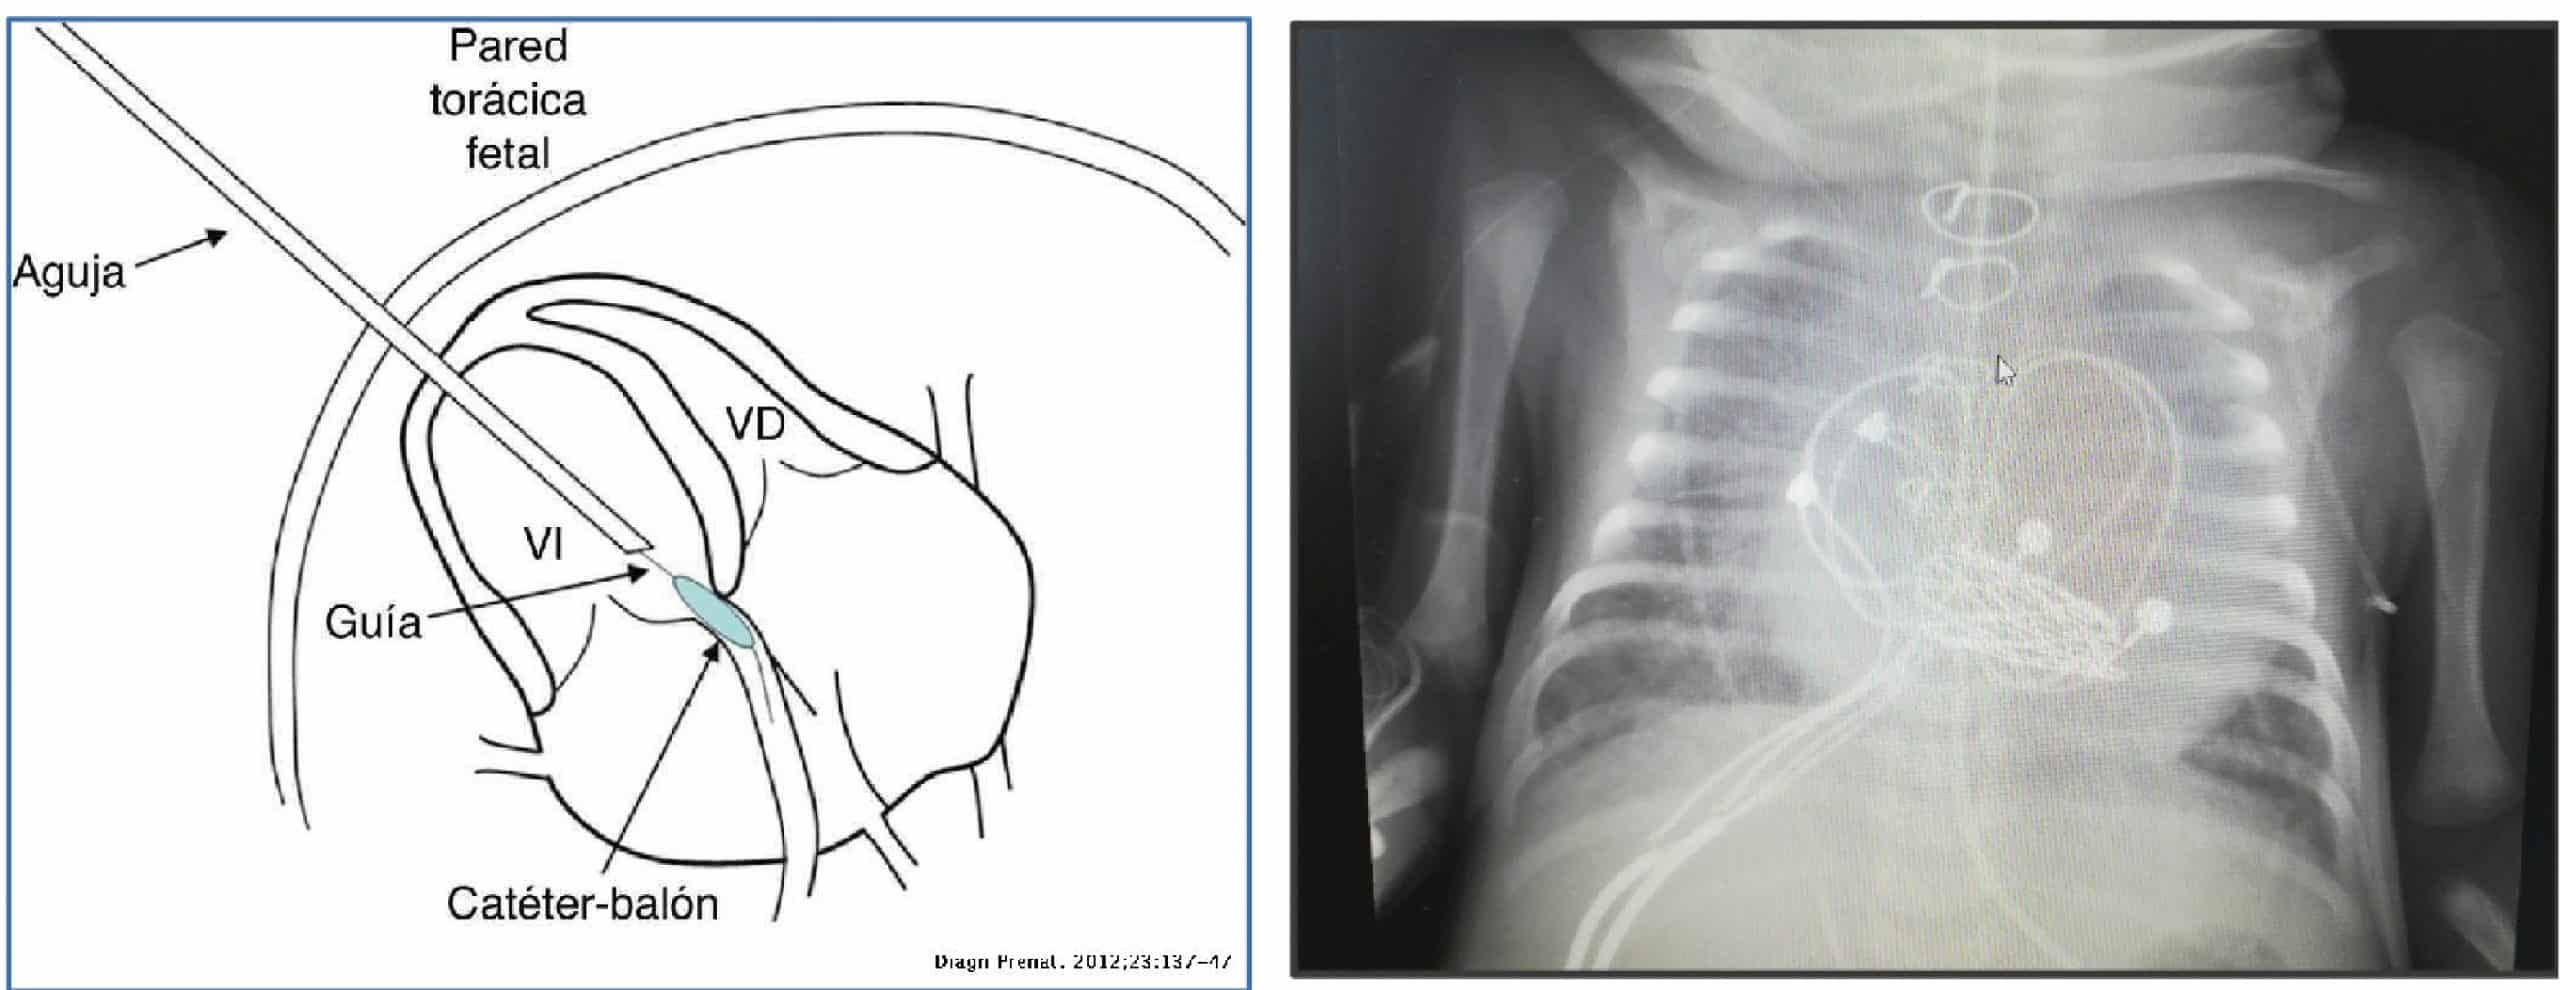

El caso que expone la doctora Victoria Ramos es el de un paciente con diagnóstico prenatal de estenosis aortica congénita grave, estenosis e insuficiencia mitral grave y fibroelastosis subendocárdica del ventrículo izquierdo, a pesar de que este, tenía un volumen adecuado.

- Se realizo una valvuloplastia fetal, con el fin de que se pudiera desarrollar la aorta ascendente, en la semana 23 de gestación, consiguiéndose una apertura de la válvula aortica de 3 mm.